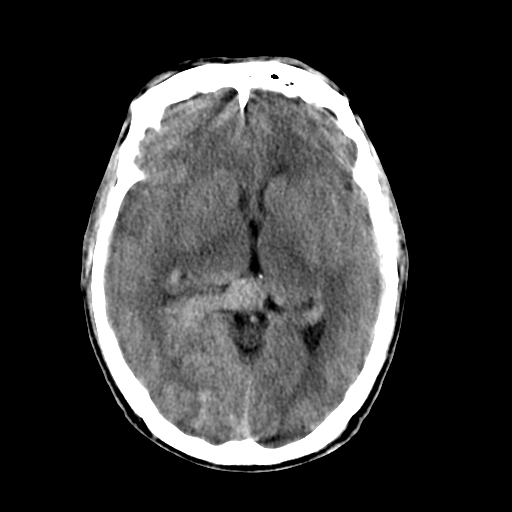

标题: CT17002:M48Y,血管畸形,血管瘤,请鉴赏! [打印本页]

男48y,头痛多年,加重一天!

典型的血管畸形---avm  -----右侧枕顶叶及侧脑室三角区等高混杂密度影夹杂少许低密影显示,无明显水肿,增强可见明显的供血动脉与引流静脉显示